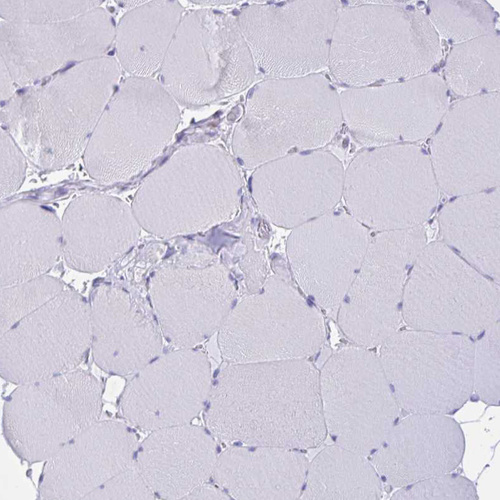

Immunohistochemistry analysis in human bone marrow and skeletal muscle tissues using HPA056183 antibody. Corresponding RNASE3 RNA-seq data are presented for the same tissues.